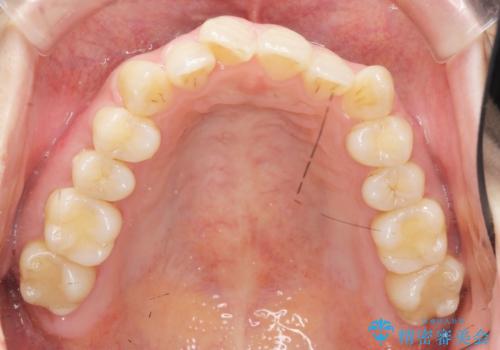

前歯のねじれを改善 マウスピース矯正インビザライン

- 目立つ前歯のねじれを改善したい、と矯正治療を希望され来院されました。

左側の奥歯は後方移動を行うことで、理想的な噛み合わせに整えるとともに、前歯の突出感も同時に改善することができました。